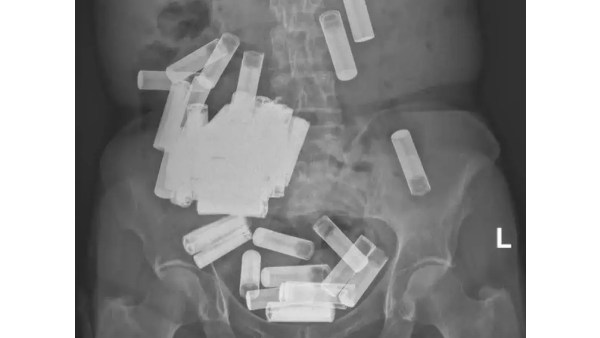

இந்த நிலையில், அயர்லாந்தில் உள்ள 66-வயது மூதாட்டி ஒருவர் பேட்டரிகளை விழுங்கியிருக்கிறார். அதுவும் ஒன்றல்ல.. இரண்டல்ல.. சுமார் 50 பேட்டரிகளை விழுங்கியிருக்கிறார். கடிகாரம், ரிமோட் போன்றவற்றிற்கு பயன்படுத்தபப்டும் ஏஏ, ஏஏஏ வகை பேட்டரிகளை அந்த மூதாட்டி விழுங்கியிருக்கிறார். தன்னைத்தானே தன்புறுத்திக்கொள்ளும் மனப்பான்மையுடன் பேட்டரிகளை விழுங்கி வந்திருக்கிறார். ஒரு கட்டத்தில் வயிற்று வலி மற்றும் உடல் உபாதைகள் ஏற்பட்டதால் மருத்துவமனைக்கு அந்த மூதாட்டியை அழைத்து சென்றுள்ளனர்.

அந்த மூதாட்டிய பரிசோதித்த வின்செண்ட் பல்கலைக்கழக மருத்துவமனையில் உள்ள மருத்துவர்கள் எக்ஸ்.ரே எடுத்து பார்த்துள்ளனர். அதில் அந்த வயதான பெண்மணியின் குடல் மற்றும் வயிறு முழுவதும் பேட்டரிகளாக இருந்ததை கண்டு அதிர்ச்சி அடைந்தனர். அறுவை சிகிச்சை செய்து பேட்டரிகளை எடுக்கலாமா? அல்லது இயற்கையான முறையில் வெளியேற மருத்துவ கொடுக்கலாமா? என ஆலோசித்த மருத்துவர்கள் இயற்கையான முறையில் வெளியேறட்டும் என அதற்கான சிகிச்சைகளை கொடுத்துள்ளனர்.

ஒருவார காலத்தில் வெறும் 5 ஏஏ வகை பேட்டரிகளே இயற்கையான முறையில் வெளிவந்துள்ளது. அதன்பிறகு எக்ஸ்ரே எடுத்து பார்த்ததில் பல பேட்டரிகள் குடல் மற்றும் வயிறு பகுதிகளில் அப்படியே இருந்துள்ளது. இதனால், அறுவை சிகிச்சை செய்து எடுப்பதே நலம் என்ற முடிவுக்கு வந்த மருத்துவர்கள் வயிற்றில் ஒரு சிறிய அறுவை சிகிச்சை செய்து 46 பேட்டரிகளை எடுத்துள்ளனர். நல்லவேளையாக பேட்டரிகள் எதுவும் வயிற்றில் இருந்து சேதம் அடையவில்லை. அப்படி எதாவது நடந்திருந்தால் அதில் உள்ள ரசாயனங்கள் உயிருக்கு ஆபத்தாக மாறியிருக்கும் என்றும் மருத்துவர்கள் தெரிவித்தனர்.

மருத்துவர்கள் இது பற்றி கூறுகையில், பெருங்குடல் பகுதியில் சிக்கியிருந்த எஞ்சிய 4 பேட்டரிகளும் மீட்கப்பட்டு விட்டதாகவும் மொத்தம் 55 பேட்டரிகள் அந்த மூதாட்டியின் வயிற்றில் இருந்து எடுக்கப்பட்டுள்ளதா தெரிவித்தனர். தன்னைத்தானே துன்புறுத்திக்கொள்ள வேண்டும் என்று வேண்டும் என்றே பேட்டரிகளை விழுங்குவது ஒரு அசாதாரண நிகழ்வு ஆகும் என்றும் தெரிவித்தனர்.